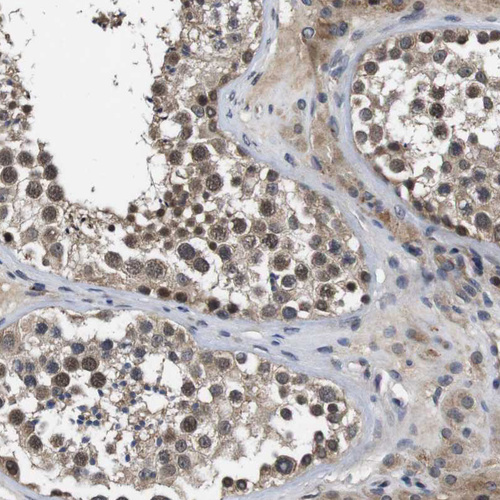

Immunohistochemical staining of human cerebral cortex shows strong nuclear positivity in neurons.